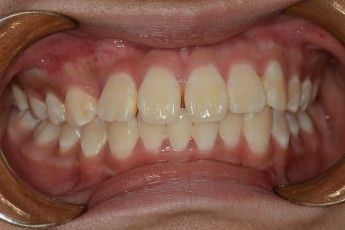

Before

After